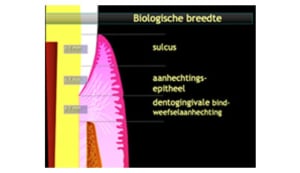

Parodontitis is een chronische, multifactoriële ontstekingsziekte met episodes van activiteit en is geassocieerd met een dysbiotische plaque biofilm, aanhechtingsverlies, röntgenologisch botverlies, aanwezigheid van verdiepte pockets en bloeding van het tandvlees na sonderen. Wanneer de balans tussen aanval en verdediging optimaal is, is er sprake van gezond tandvlees. Wanneer deze balans wankel verloopt is er sprake van gingivitis en wanneer het mis loopt is er sprake van parodontitis. Er zijn verschillende vormen van parodontitis namelijk; acute parodontale laesies (zoals necrotiserende parodontale aandoeningen en een parodontaal abces), parodontitis als directe manifestatie van een systemische aandoening en parodontitis. Om parodontitis te classificeren wordt gekeken naar de uitgebreidheid, ernst en progressie.